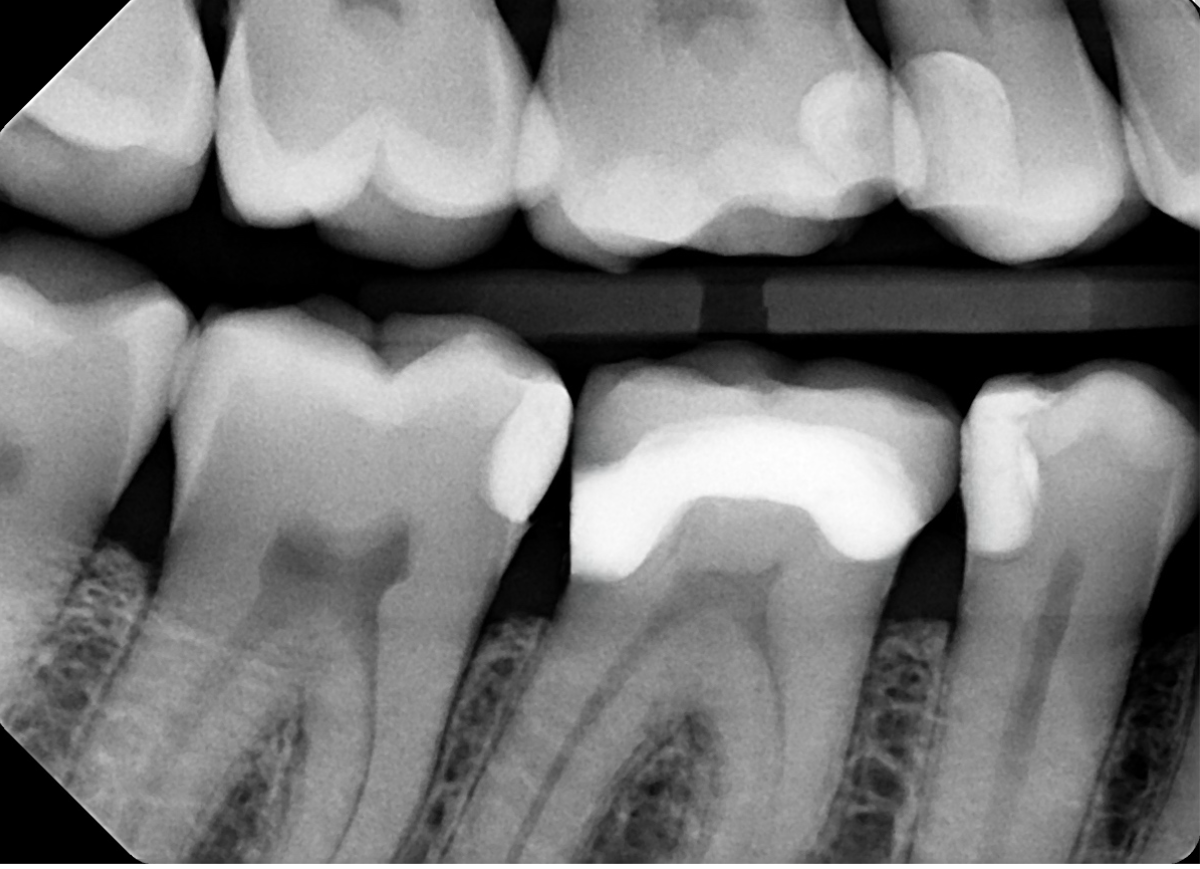

15. On which surface a recurrent caries can be detected?

16 / 35

16. On which surface a recurrent caries can be detected?

Mesial tooth # 3.7 is not recurret caries, the recurrent caries in proximal always starts from the gingival of the proximal box